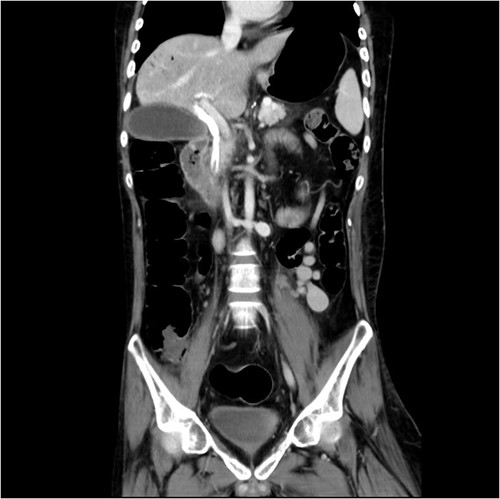

And then, a 7 French bostone scientific plastic stent was inserted over the guide wire for bile diversion. However, hemobilia was noted to be draining out from the stent right after. After reviewing the image, we realised that PVC was probably made (Fig. 3). After discussing with the general surgeon, we decided to arrange immediate surgical exploration to check for collateral damage and remove the CBD stones for cholangitis resolution. The stent was thus left inside for surgical guidance. Before the surgery, abdomen computed tomography (CT) was done and revealed retained contrast medium in the bile duct (Fig. 4) and malposition of the CBD internal stent with upper portion in the main portal vein (Fig. 5).

Fluoroscopy image showed the plastic stent penetrated through the CBD.

Just after ERCP, the abdominal CT showed retained contrast medium in bile duct.